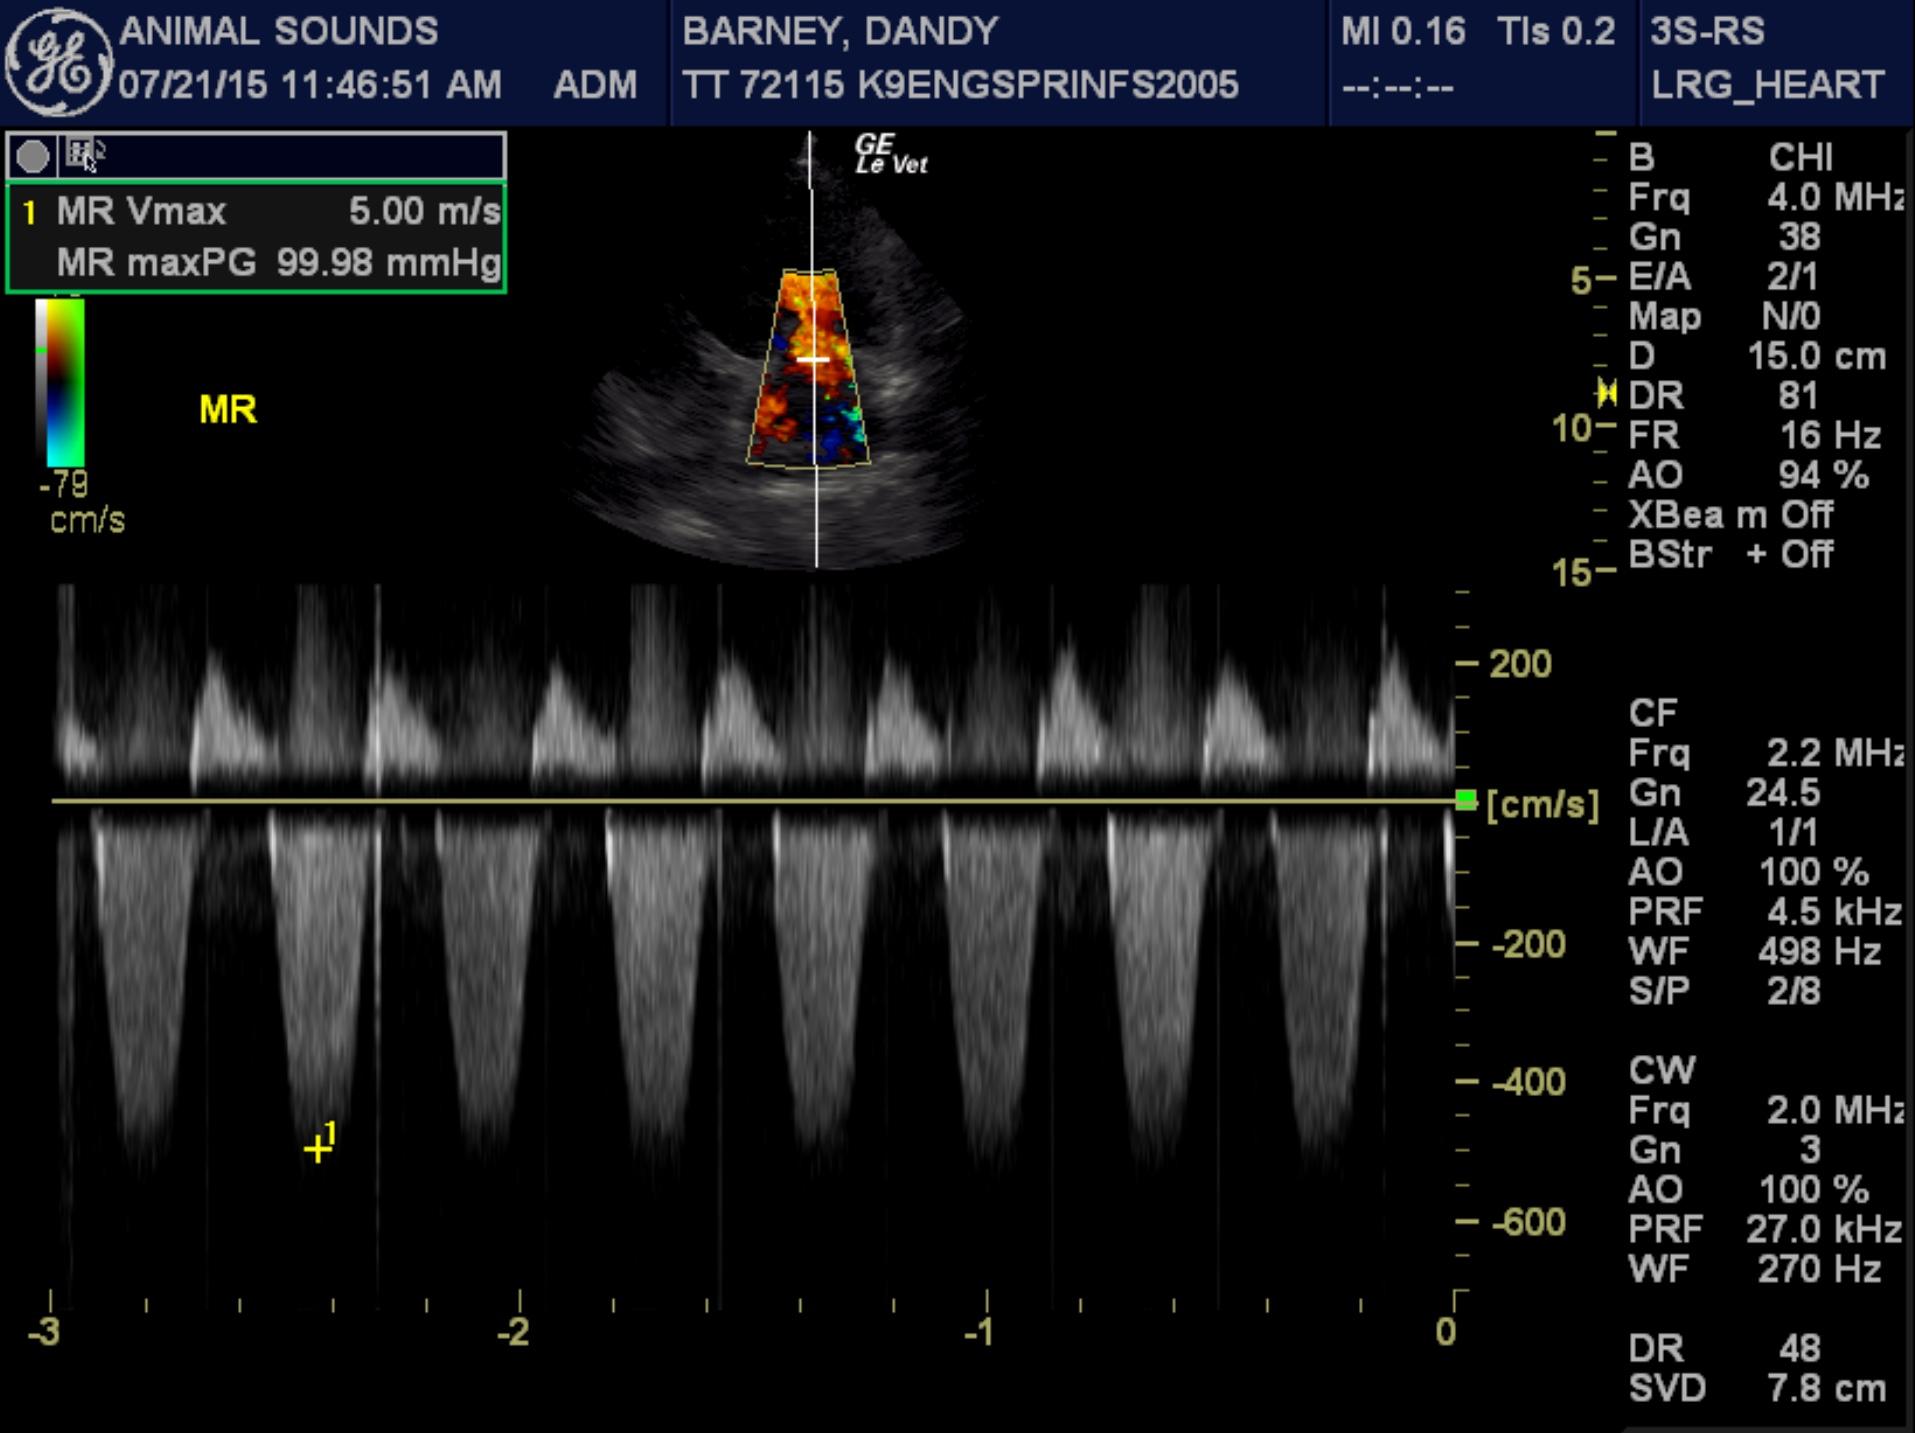

Echocardiogram findings: There is moderate to severe left ventricular dilation. The mitral valve appears normal, though a mild jet of central mitral regurgitation is present. Left ventricular systolic function is globally depressed. The aorta and aortic valve are normal. Right atrial and right ventricular dimensions are normal. The tricuspid valve appears normal, though trace physiologic tricuspid regurgitation is present. The pulmonary artery and pulmonic valve are normal. No pericardial effusion or cardiac masses are seen.

LVOT Vmax – 1.55 m/s

This examination demonstrates global left ventricular systolic dysfunction, consistent with dilated cardiomyopathy. Secondary to the patient’s myocardial dysfunction, she has severe left ventricular dilation, as well as moderate to severe left atrial dilation, and it appears that she is in mild congestive heart failure based on her thoracic radiographic findings. Given the severity of her cardiac disease, it appears very likely that this is the cause of her arrhythmia.